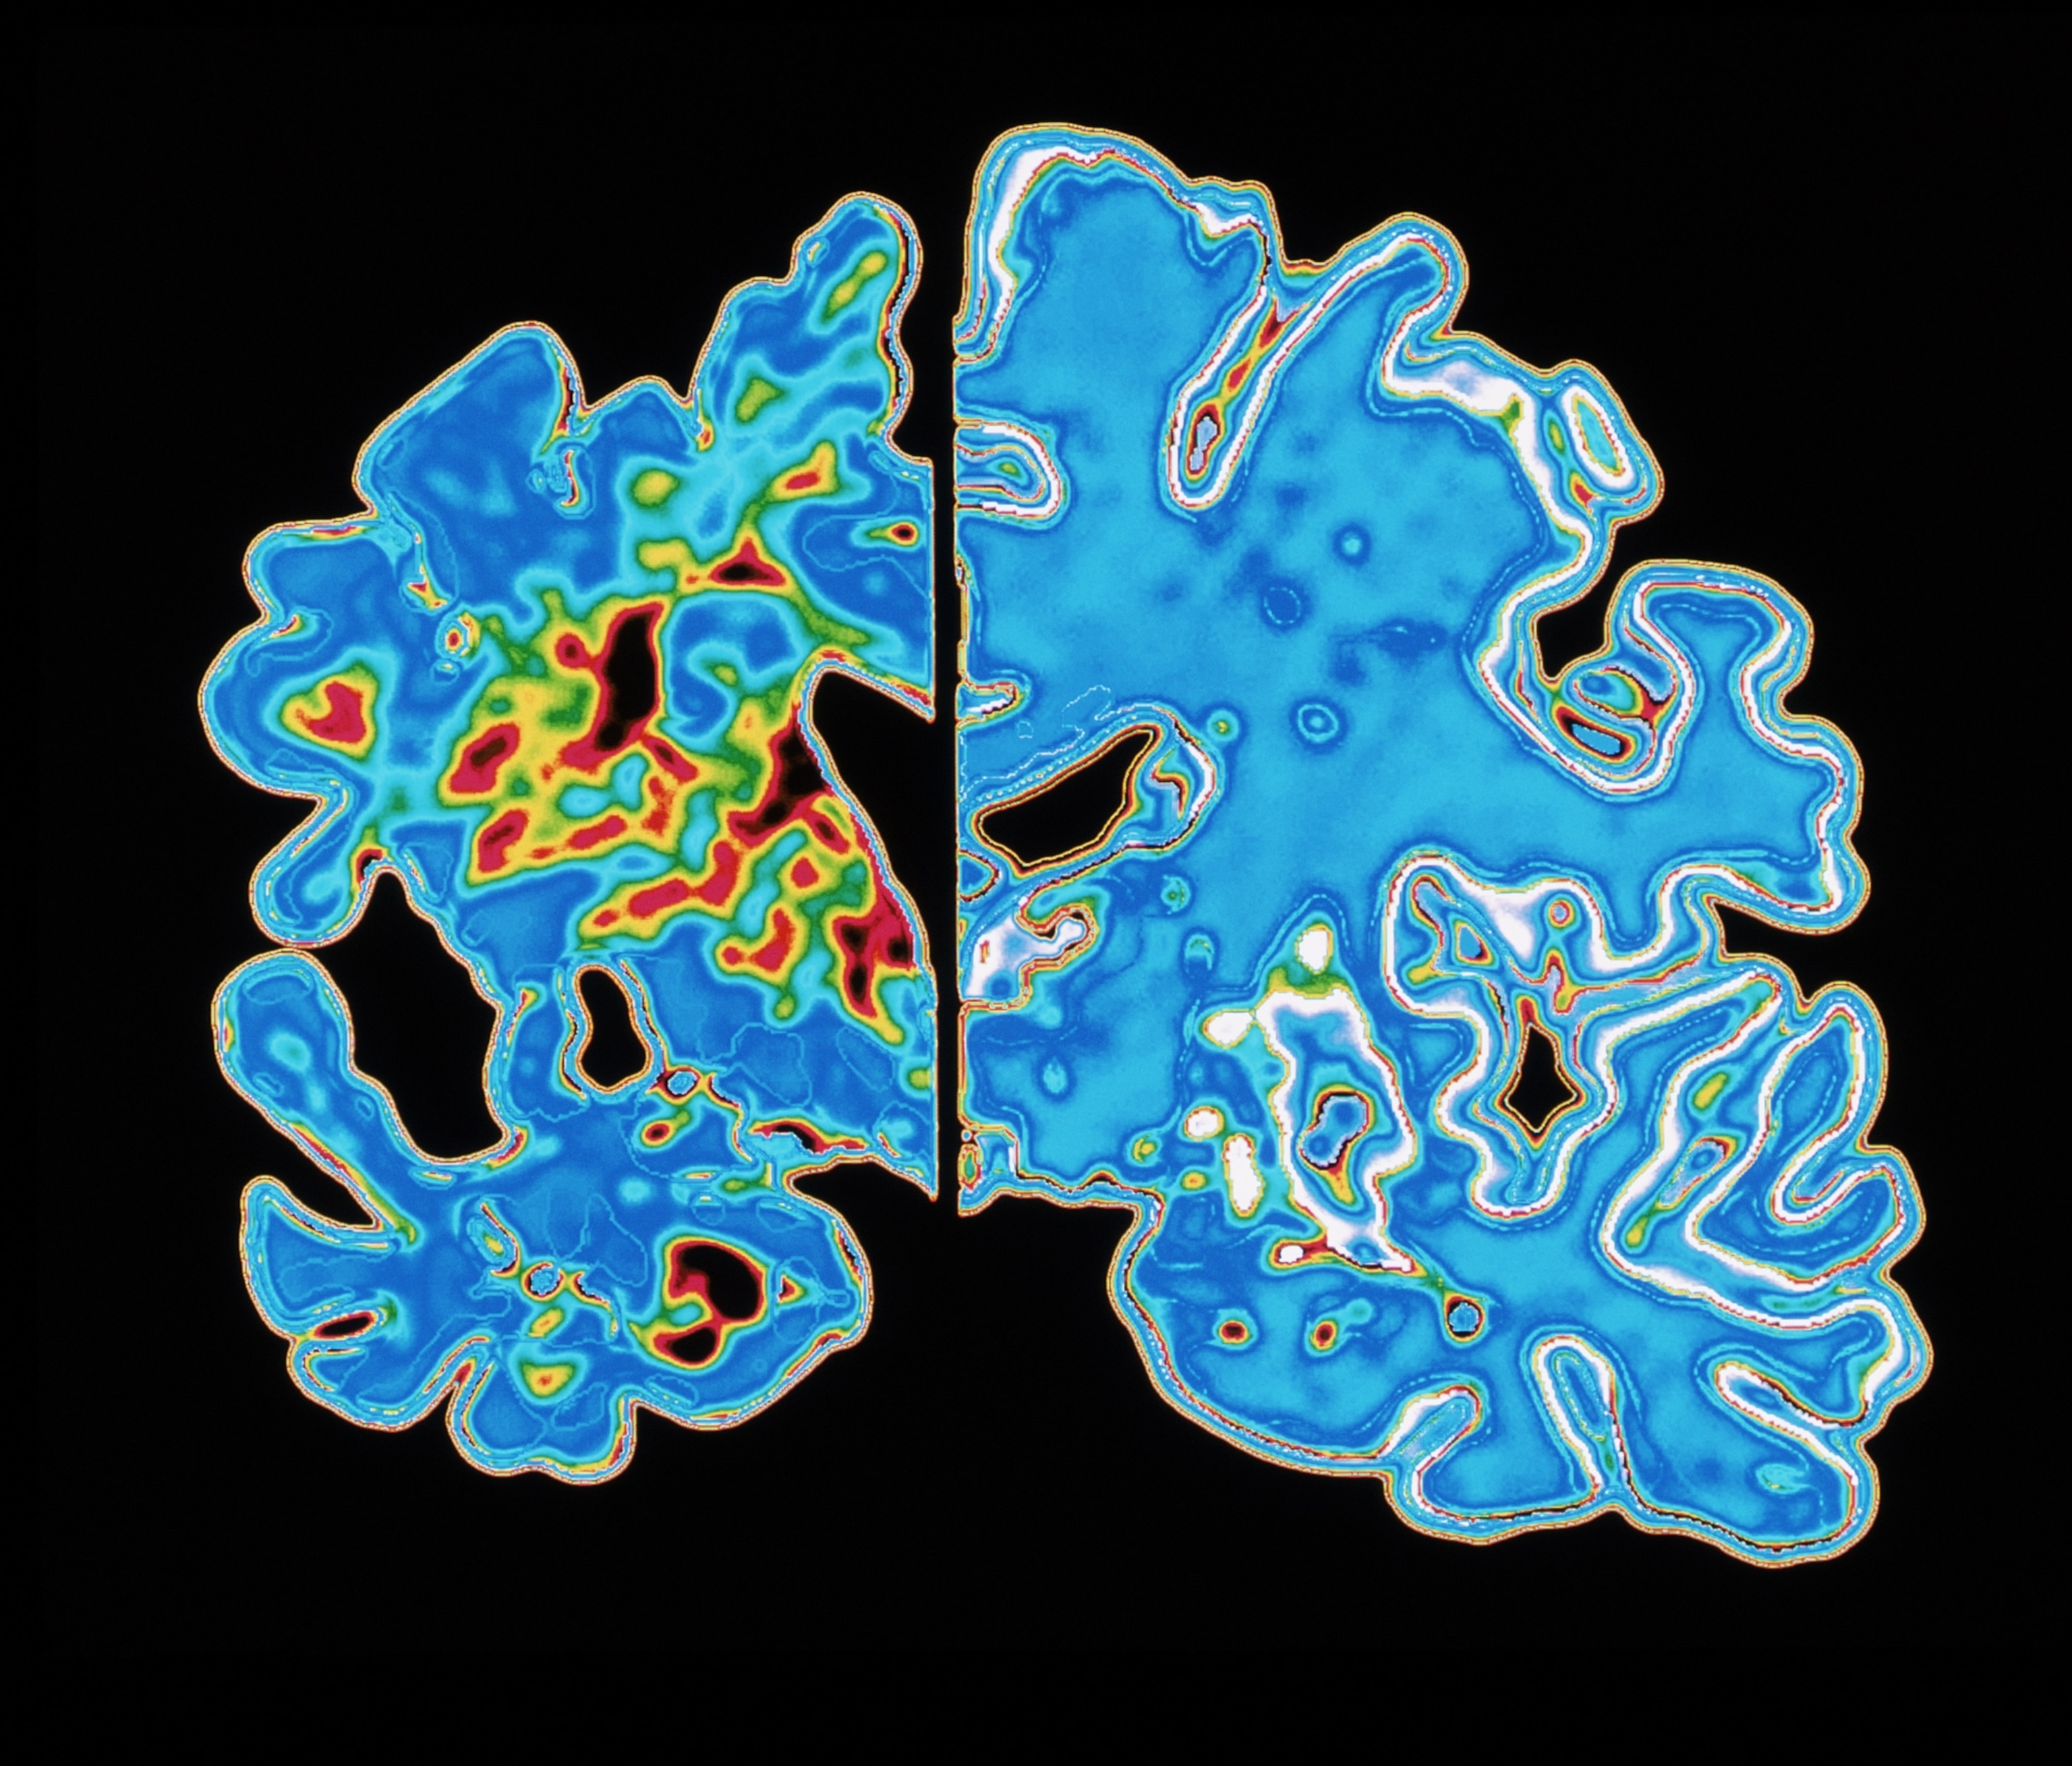

This graphic compares the brain of an Alzheimer patient (at left) with a normal brain (at right). Apart from a decrease in brain volume, the defining characteristics of Alzheimer’s are tangled protein filaments in nerve cells as well as a buildup of beta-amyloid protein called amyloid plaques.

Amyloid plaques have long been thought to cause Alzheimer’s disease by damaging neurons in the brain. However, new research suggests that the immune system’s response to the plaques may be the real culprit.